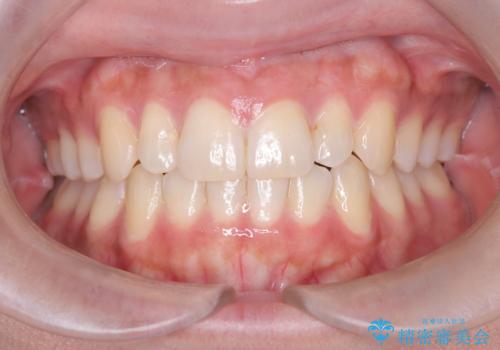

凸凹を綺麗にしたい。表側ワイヤー矯正

担当医 河口智英